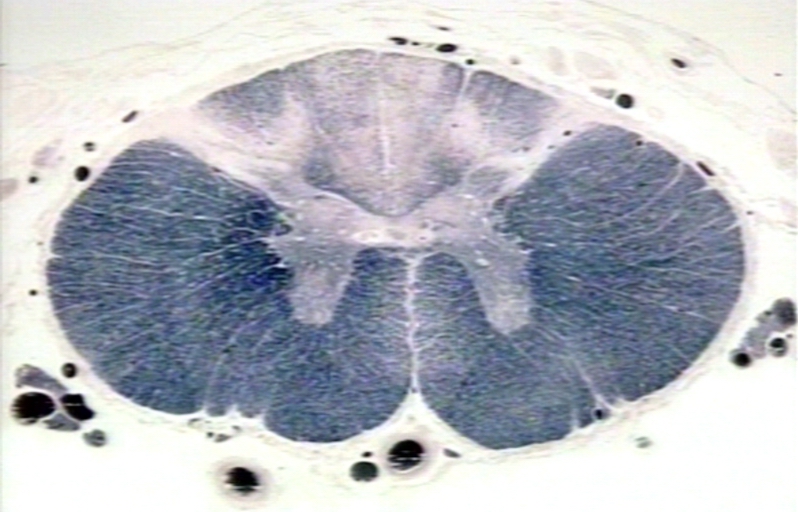

¿Qué es Tabes dorsal?

Tabes dorsal es una manifestación específica de la neurosífilis tardía, una condición provocada por la infección del sistema nervioso central con la bacteria Treponema pallidum pallidum, que es una subespecie…